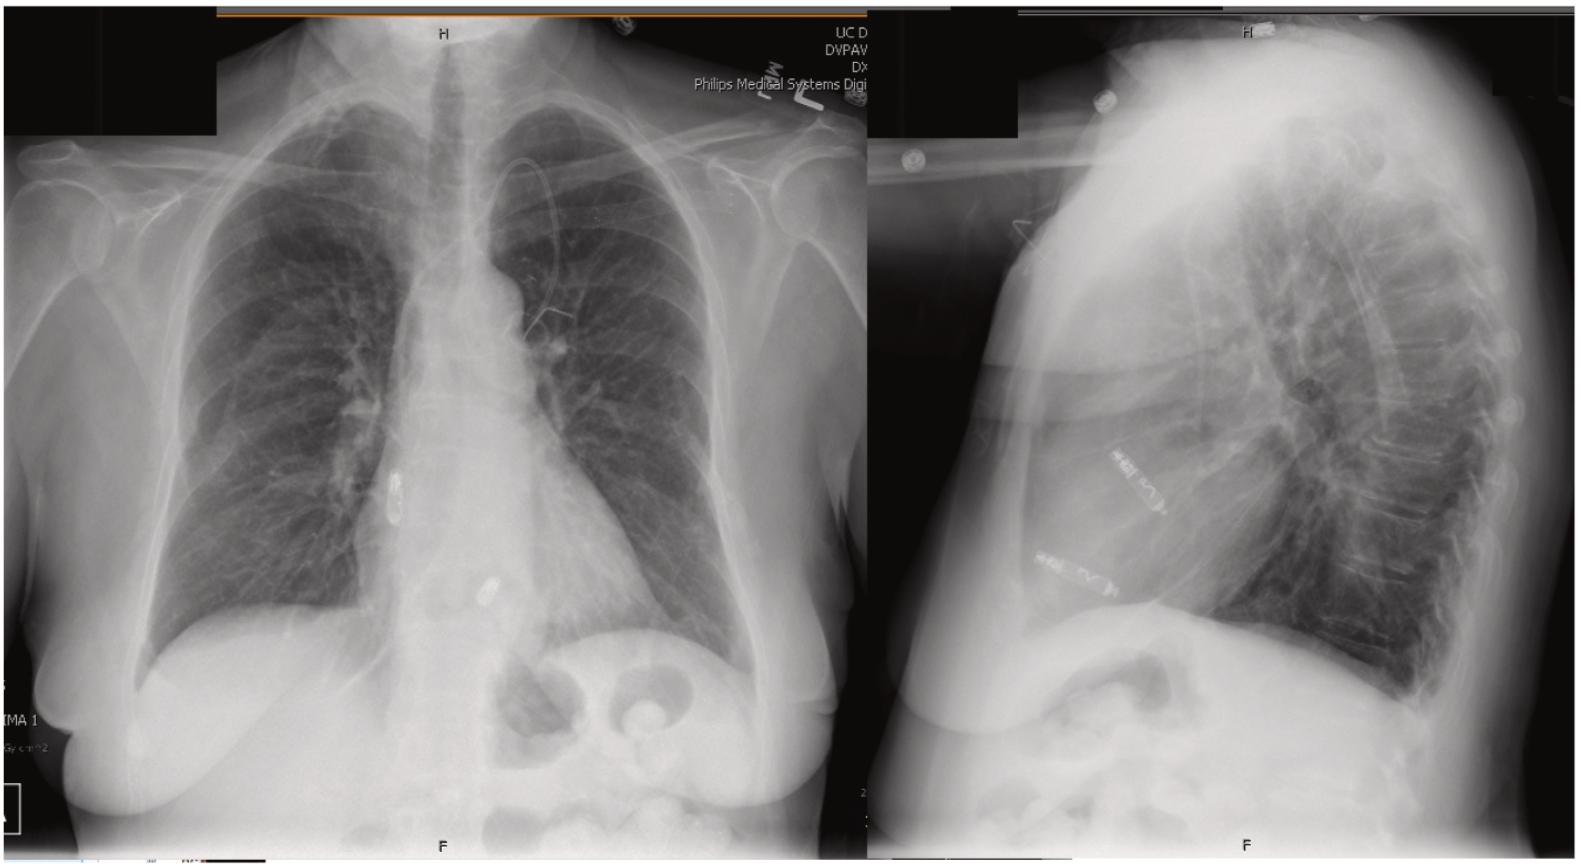

· 术后放射学成像显示,AVEIR™ VR成功植入室间隔,AVEIR™ AR成功植入右心耳基底部(图4);

图4 AP位和左侧位术后胸片

·术后30天随访显示,心房起搏占比78%,心室起搏占比<0.1%;AVEIR™ AR起搏器预计使用寿命为12.5年,AVEIR™ VR起搏器为14.8年;阈值、阻抗和感知功能均稳定(表1),频率应答功能开启。